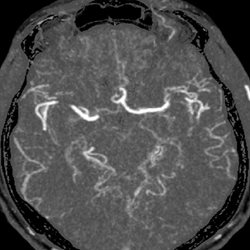

Arterial Case 09B - Hyperacute Stroke

42 year old male with right sided numbness and neck pain; history of seizures and hypertension. (follow up study)